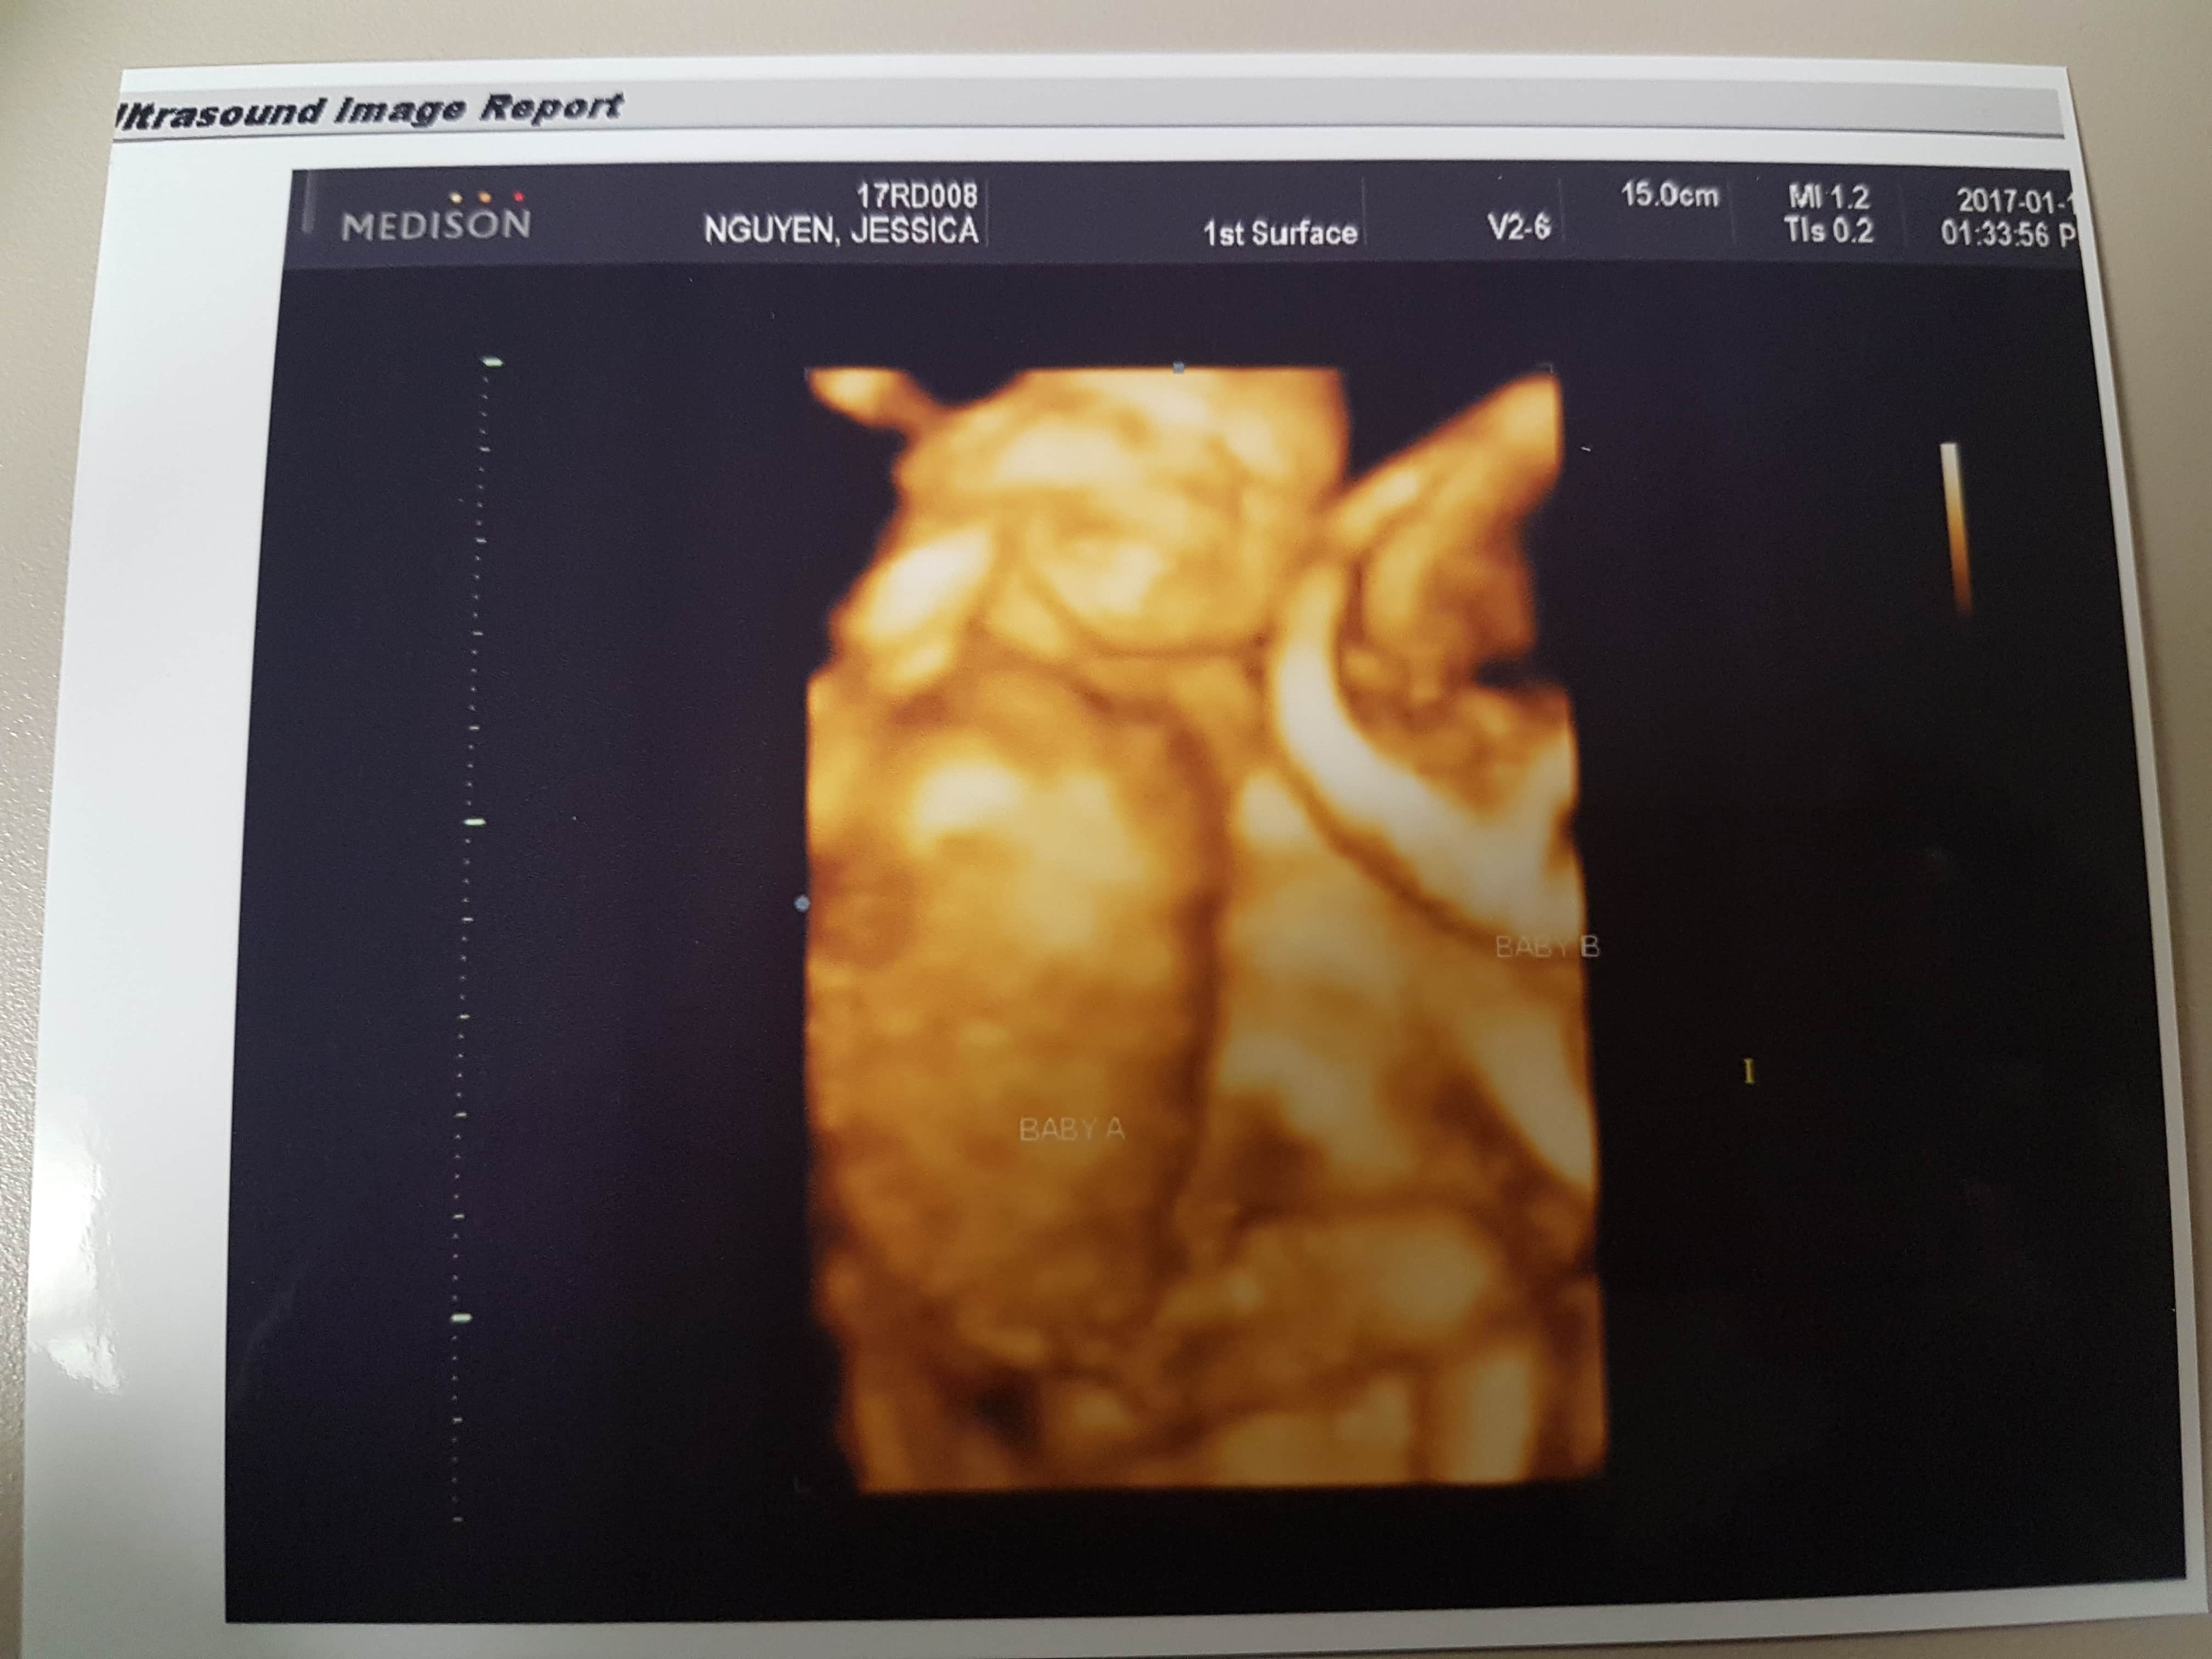

Ultrasound Photos at 18 Weeks Pregnant With Twins